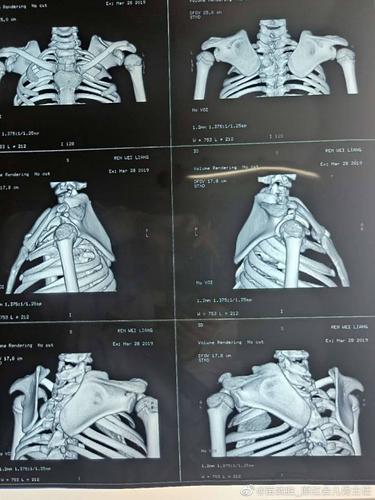

先天性高肩胛术后照片,高肩胛骨症孩子图片

肩胛骨专用板治疗浮肩损伤病例分享

女16岁,合并有先天性高肩胛

近期做的先天性高肩胛术前术后照片

高肩胛骨症孩子图片

先天性高肩胛骨症图片